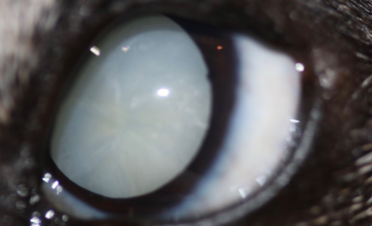

Miso es una hembra de Jack Russell de 12 años de edad que acudió a IVO para una primera valoración de cataratas bilaterales.

Sus propietarios habían notado un inicio de catarata en el ojo izquierdo hacía un año y medio aproximadamente, y en los últimos dos meses pérdida de visión por la noche y durante el día, coincidiendo con la aparición de una catarata en el ojo derecho.

En el caso de Miso, la catarata del ojo derecho estaba más desarrollada que la del izquierdo, pero se operaron ambas el mismo día para que su recuperación fuera más rápida y solo tuviera que pasar por quirófano una vez.

Durante las visitas postoperatorias no se observaron complicaciones. Miso tuvo una muy buena recuperación visual de ambos ojos, tan rápida que enseguida quiso volver a jugar con la pelota.